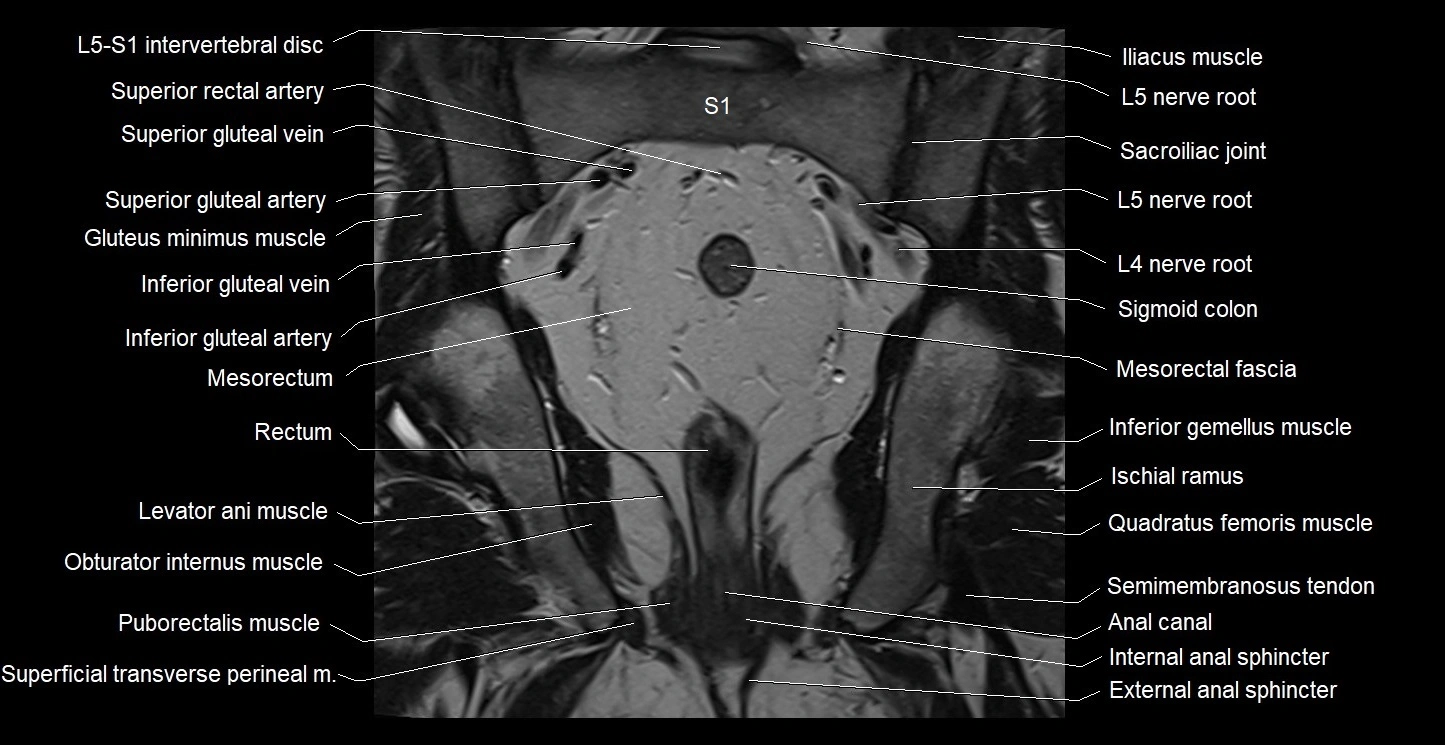

- Anal canal

- Conjoint tendon of biceps femoris & semitendinosus

- External anal sphincter

- Gluteus maximus muscle

- Gluteus minimus muscle

- Gracilis muscle

- Iliococcygeus muscle

- Inferior gemellus muscle

- Inferior gluteal artery

- Inferior gluteal vein

- Internal anal sphincter

- Ischiopubic ramus

- L5–S1 Intervertebral disc

- Levator ani muscle

- Lumbosacral trunk

- Mesorectal fascia

- Mesorectum

- Obturator internus muscle

- Puborectalis muscle

- Quadratus femoris muscle

- Rectum

- Sacrospinous ligament

- Sciatic nerve

- Semimembranosus tendon (proximal)

- Sigmoid colon

- Superficial transverse perineal muscle

- Superior gluteal artery

- Superior gluteal veins

- Superior rectal artery